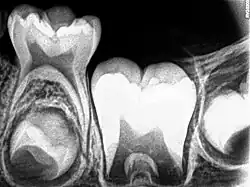

Después del tratamiento de pulpotomía, la pulpa radicular debe permanecer asintomática sin ningún signo o síntoma clínico adverso como sensibilidad, dolor o inflamación. En las radiografías no debe haber evidencia postoperatoria de reabsorción radicular patológica. Debe haber ausencia de signos clínicos de infección e inflamación y ningún daño al diente sucesor . [1] Sin embargo, las radiografías juegan un papel muy importante para comprobar si se puede realizar una pulpotomía en el diente primario. Por ejemplo, se consideran aspectos como la extensión de la caries en el diente primario y el desarrollo del diente permanente sucesorio.